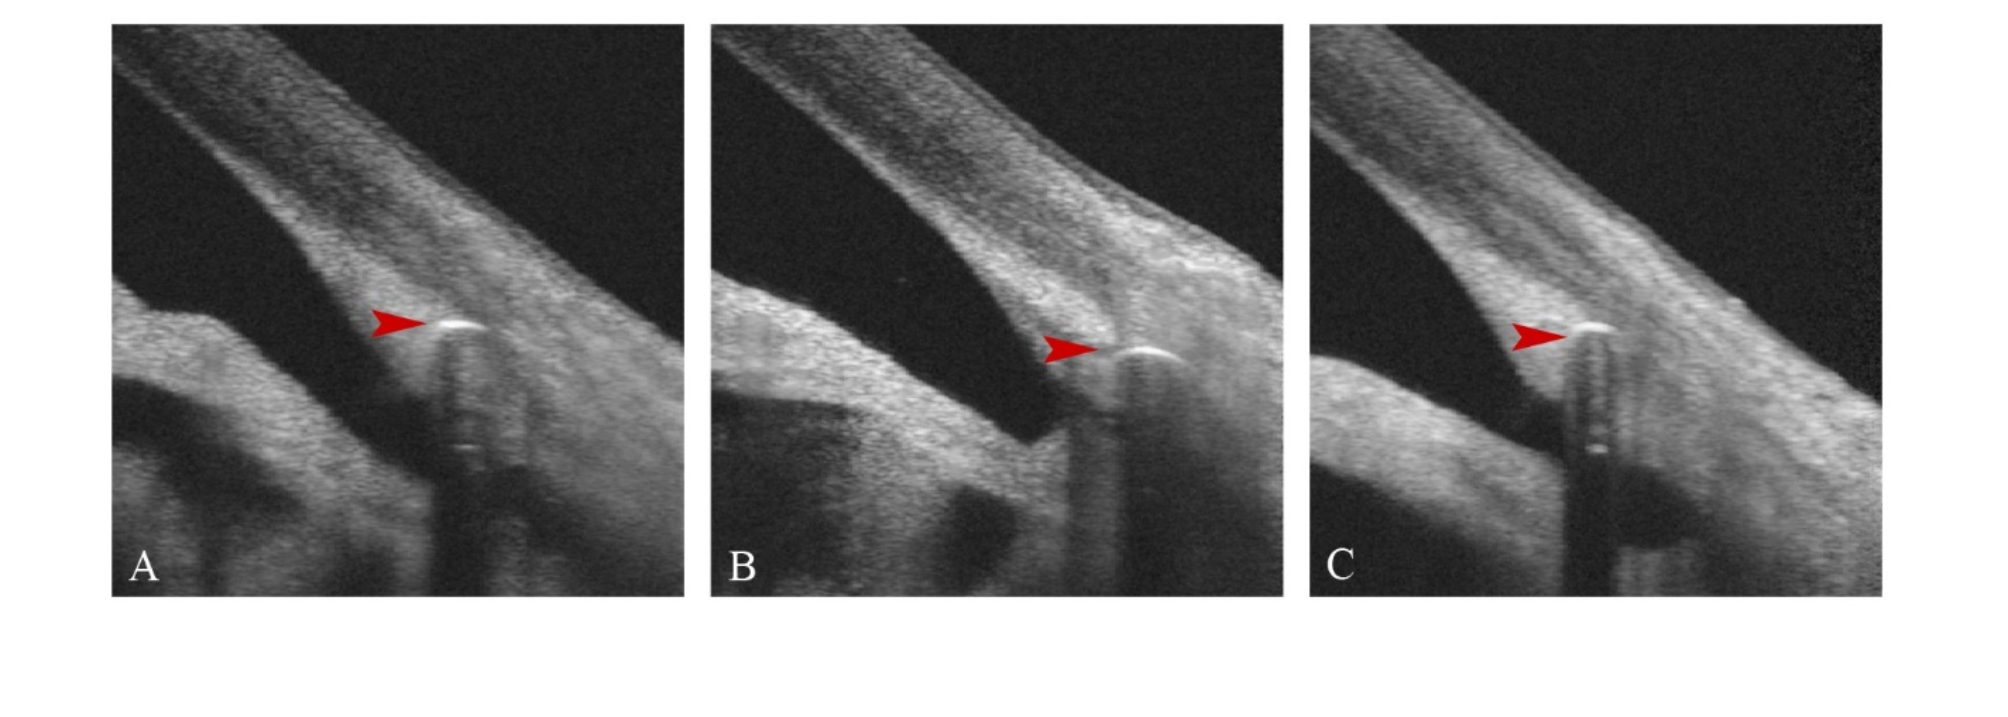

Fig. 2

(A) OCT images of the anterior segment of Wistend eye 1 week after surgery; (B) OCT images of the anterior segment of Wistend eye 1 month after surgery; (C) OCT images of the anterior segment of Wistend eye 6 months after surgery.